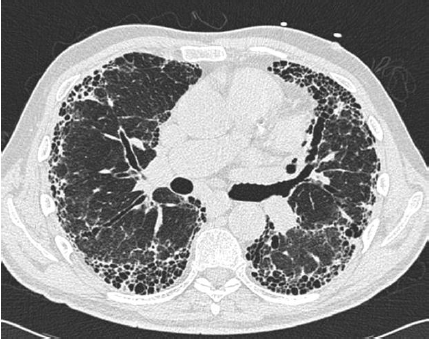

A tomografia computadorizada de alta resolução é de grande ajuda no diagnóstico das doenças pulmonares. O principal diagnóstico relacionado à imagem abaixo é: